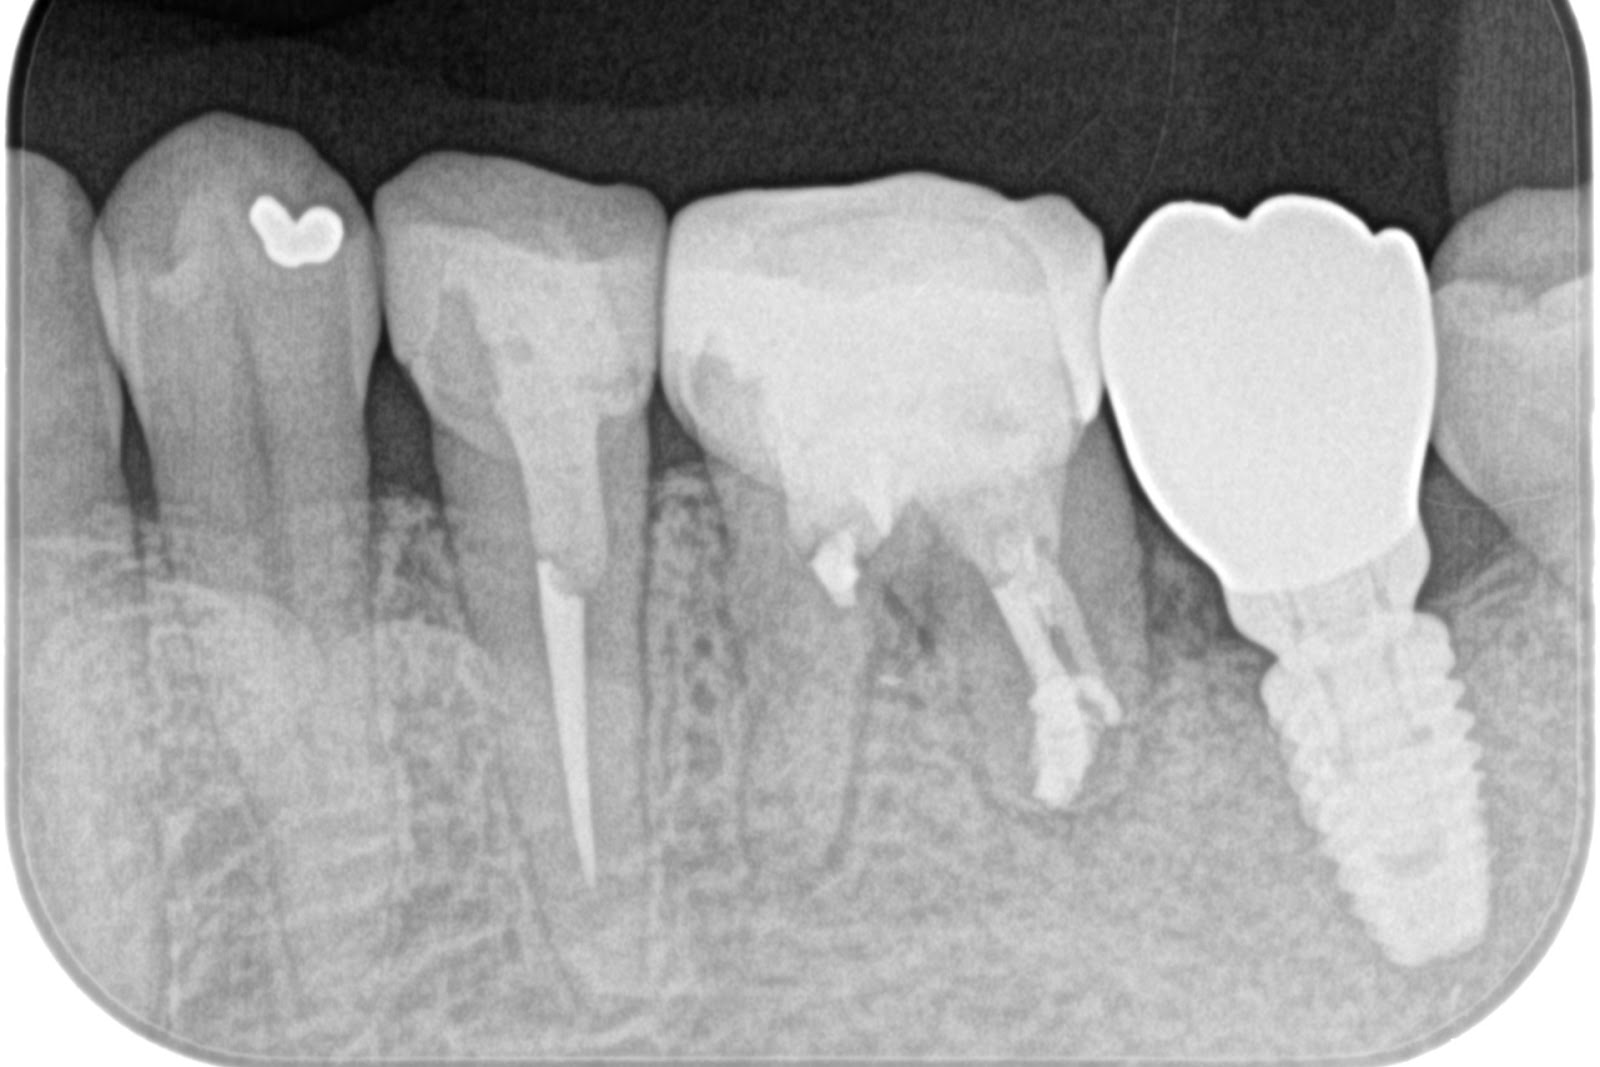

手術後(左下)

上部構造セット後(左下)